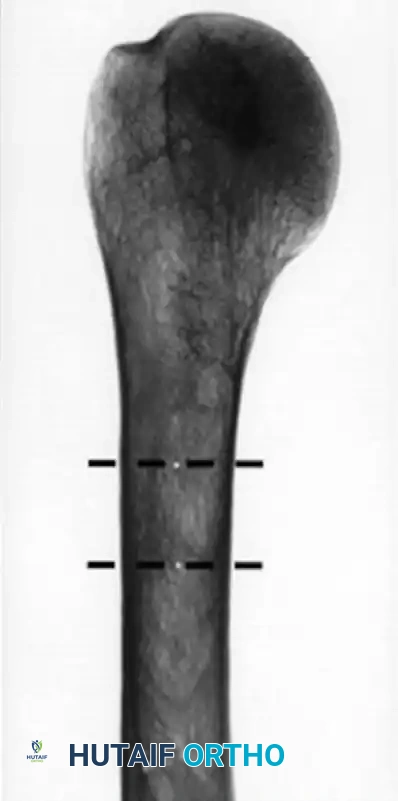

قياس كثافة العظام وسماكة القشرة

تعتبر سماكة قشرة عظمة العضد مؤشراً قوياً على كثافة العظام. إذا كانت العظام هشة جداً وقشرتها رقيقة، فقد لا تتمكن المسامير الطبية من التثبيت فيها بقوة. في هذه الحالات، قد يفضل الجراح استخدام تقنيات بديلة مثل الخياطة العظمية أو اللجوء إلى المفاصل الصناعية بدلاً من الشرائح والمسامير التقليدية.

إليك بعض الصور الإشعاعية والرسوم التوضيحية الإضافية التي توضح أشكال التثبيت الجراحي المختلفة لكسور أعلى عظمة العضد